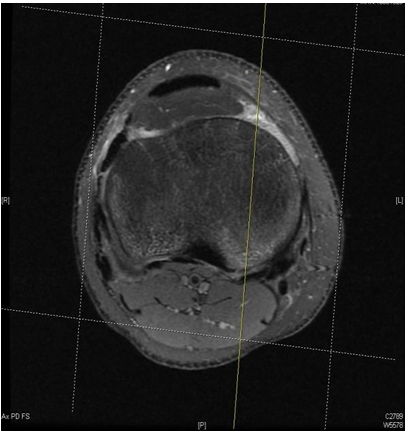

A sagittal T2 MRI cut in the middle of the medial tibial compartment was chosen for all patients to measure the PTS angle. First, the PTS angle was measured by drawing an intramedullary line parallel to the volar cortex of the tibia, and a perpendicular line is drawn over our first line. Then, a third line to be drawn between the highest bony tips of the anterior and posterior aspect of the tibial plateau. Finally, the second and third line is measured angle delineated the posterior tibial slope (Figure 1 & 2).

Figure 1 Chosen cut for middle compartment.